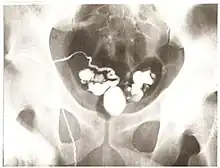

Vasography is an X-ray study of the vas deferens to see if there is blockage, oftentimes in the context of male infertility.[1] An incision is made in the scrotum, contrast is injected in the vas deferens, and X-rays are taken from different angles.[1] Thus, it is an invasive procedure and carries risk of iatrogenic scarring and obstruction of the vas.[2] Vasography has traditionally been considered the gold standard imaging modality for evaluating the seminal tract patency.[3]

Vasography was first described by Belfield in 1913, where a vasotomy was initially done and the vas deferens was subsequently intubated.[4][5] After almost 40 years of being overlooked, Boreau revived the procedure in the 1950s.[4] Then, vasography was somewhat overused for various fertility disorders and other diseases such as tuberculosis, prostate cancer, hemospermia, and compressive fibrolipomatosis, without considering the possible risks and complications from the procedure.[4] Today, vasography is used to determine the location of obstruction in azoospermic patients who have demonstrated spermatogenesis by testis biopsy.[6]